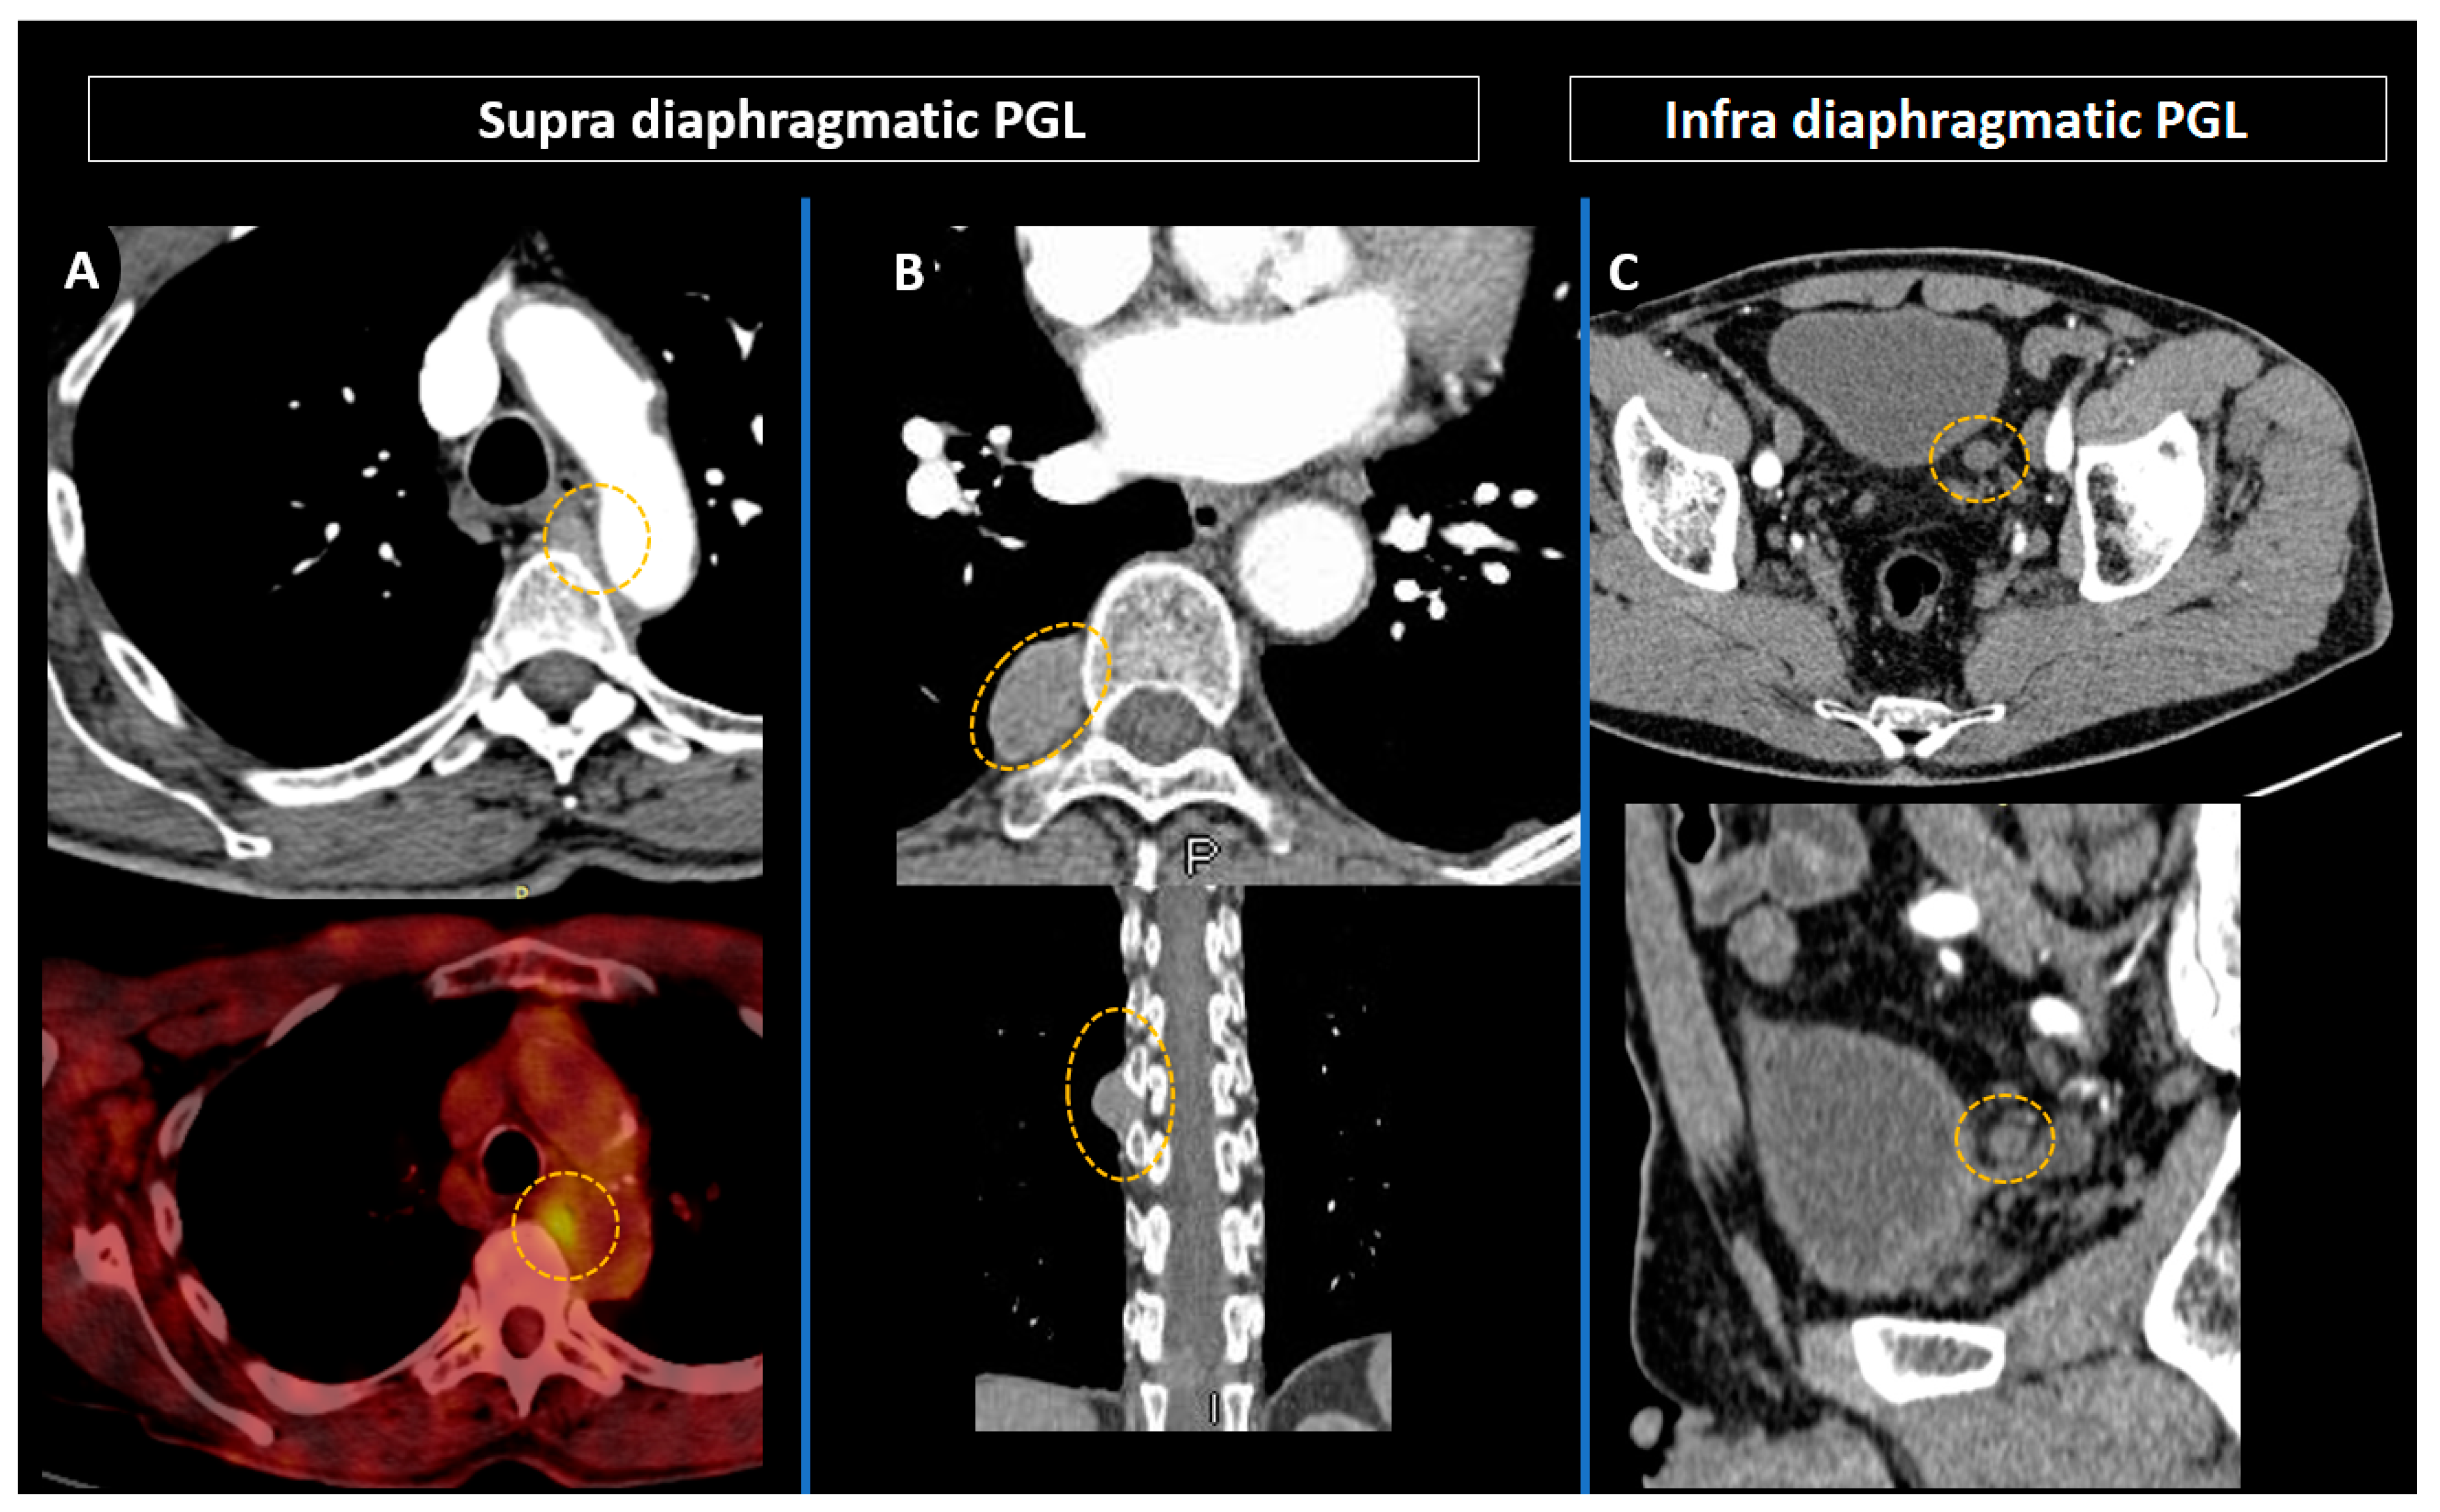

3.4. Pheochromocytomas and Paragangliomas: Variable Morphological Characteristics Using Anatomical Imaging

3.5. Head and Neck Parangangliomas: Specific Concerns

4.2. Contributions of Computed Tomography Using Dopamine and Glucose Analogues

4.3. Positron Emission Tomography with Computed Tomography Using Somatostatin Analogues